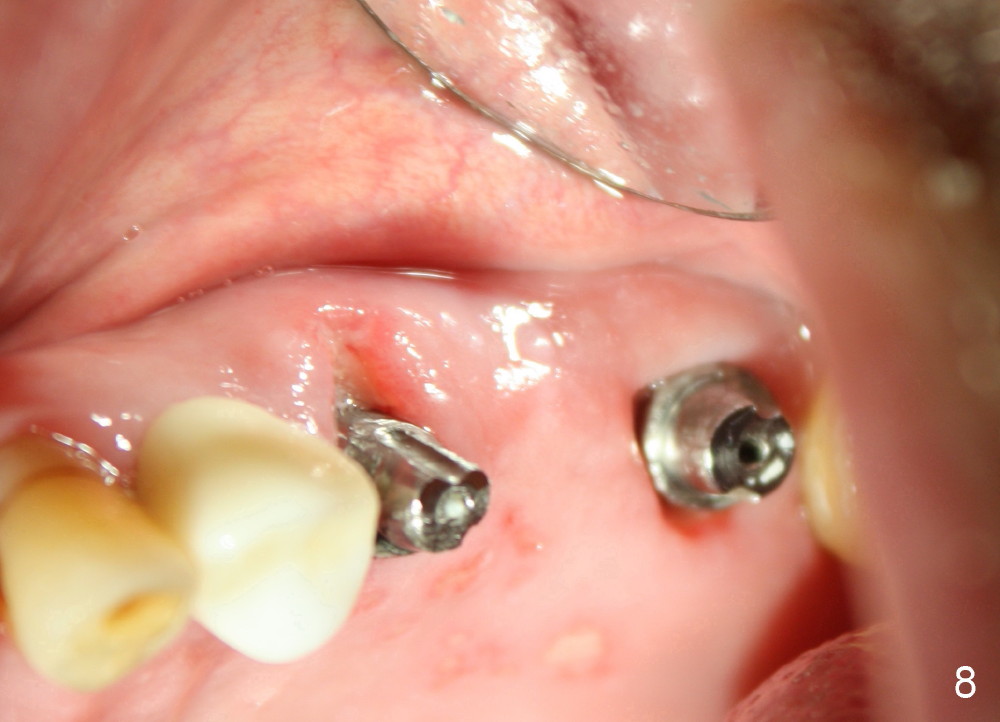

A 84-year-old man has a failing bridge.  A short implant was placed at the pontic site 5 months ago (Fig.1, taken 2 months postop).  The bridge was temporarily recemented.  It is planned at next appointment to extract #13, uncover the implant at pontic and save #15 if possible.  When the bridge is removed, the tooth #15 is also found non salvageable (Fig.2). The root stump of #15 is oval, 5x10 mm.  Preop PA shows that the 2nd molar has two roots (Fig.1: *).  When the tooth is extracted, the septum is found wide buccolingually (Fig.3: S, between the buccal (B) and palatal (P) sockets).  Osteotomy is formed in the septum with combination of drills and osteotomes, followed by insertion of taps (Fig.4).  Finally the osteotomy (Fig.5 O) in the septum (S) of #15 deviates into the buccal (B) socket.  When the implant is placed (Fig.6), it deviates buccally slightly (Fig.7).  The remaining sockets are filled by bone graft (Fig.7 G).  Immediate provisional bridge is fabricated after placement of abutments (A).  The main purpose of the provisional at early stage is to hold bone graft in place.  There is no occlusal contact with the opposing dentition,  Due to time constraint, the uncovering of #14 is postponed.  The provisional dislodges 2-3 days postop.  The patient returns for recementation 5 days postop; the sockets have initially healed (Fig.8,9, as compared to Fig.7).